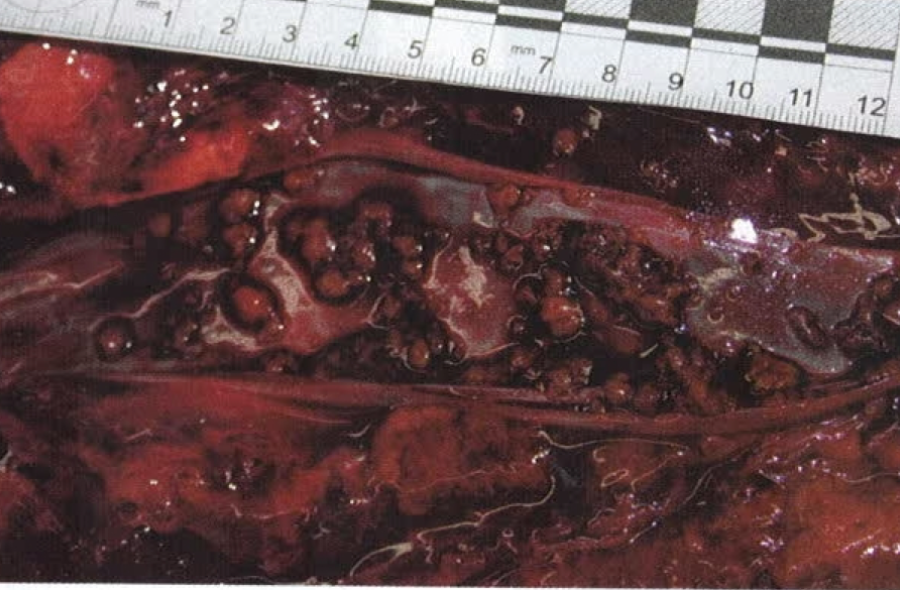

fat embolism 2 post gluteal lipoinjection